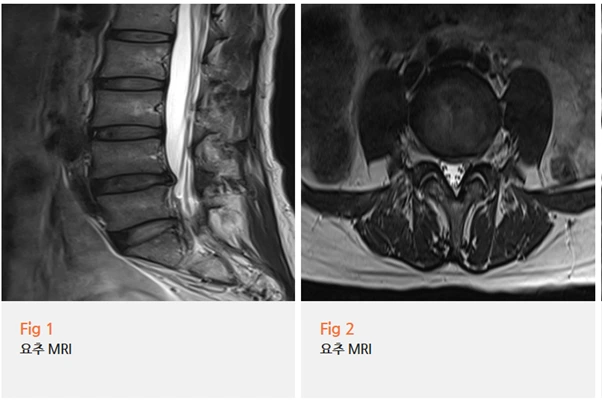

반면 고관절 자체에는 구조적인 문제가 없었죠.

%EA%B7%B8%EB%A6%BC3.png?type=w966

그러니까 고관절이 아팠던 게 허리에서 내려오는 신경 압박 때문이었던 거예요.

동네 병원에서 주사를 맞았을 때 일시적으로만 좋아졌던 이유도 이해가 됐어요.

고관절 주변을 치료했으니 당연히 근본 원인에 접근하지 못했던 거고,

그러니 금방 다시 통증이 돌아올 수밖에 없었던 거죠.